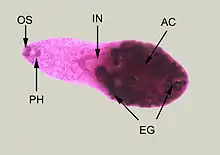

| Adult specimen stained with carmine | |

Minute teardrop-shaped flukes found in the small intestines of fish-eating birds and mammals. The eggs are hard to tell apart from other related species so there is no accurate estimate of human infection. H. heterophyes is a small trematode, ranging up to 1.4mm long and 0.5mm wide.[4] It is covered with scale-like spikes and those spikes can range from 50–62.[6] Their pharynx is completely developed and connected to the cecum of the small intestines. Their sucker (mouth) is covered with spikes and its covering the genital opening. This means, they share one hole for eating and reproduction. Their testes is located at the posterior of the parasite and the testes are side by side.[4] The ovaries are located in the medial of the parasite, right above the testes.[4] The ventral sucker also known as the acetabulum is located at the ventral of the parasite.[4] The ventral sucker helps them attach to the host. Morphology can change depending on what fish it lives on.